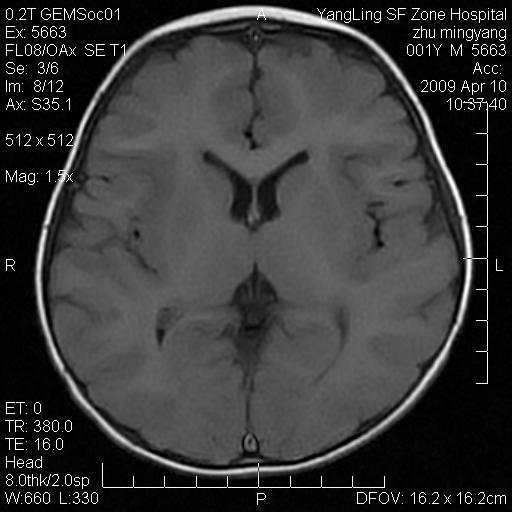

患者:1岁半,两天前外伤收住我院,ct检查小脑占位

考虑星形细胞瘤,建议增强

髓母细胞瘤或血管母细胞瘤,增强后可以鉴别;影像资料见 <。鱼博浪老师的《中枢神经系统ct与mr鉴别诊断》 小脑部肿瘤章节。

髓母细胞瘤或血管母细胞瘤!支持!

支持考虑髓母细胞瘤

考虑----髓母细胞瘤可能性大

考虑髓母细胞瘤或室管膜瘤。

支持髓母细胞瘤。

考虑髓母细胞瘤。

考虑髓母细胞瘤或星形细胞瘤

考虑髓母细胞瘤.

考虑髓母细胞瘤可能性大。

小脑肿瘤.考虑髓母细胞瘤可能.

就病灶部位及临床资料首先考虑髓母.